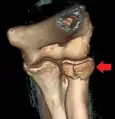

Radial head fracture (red arrow) with posterior and anterior sail sign (blue arrows)

Radial head fractures are diagnosed from a clinical assessment and diagnostic imaging. Clinical assessment may include pain or tenderness at the radial head, bruising, swelling, and a limited range of motion of the injured elbow.[2] Diagnostic imaging may include ultrasound, plain radiography (x-ray imaging), Computed tomography scan (CT), and magnetic resonance imaging (MRI).[2][4] A fat pad sign may be present on diagnostic imaging and may indicate a radial head fracture.[5]